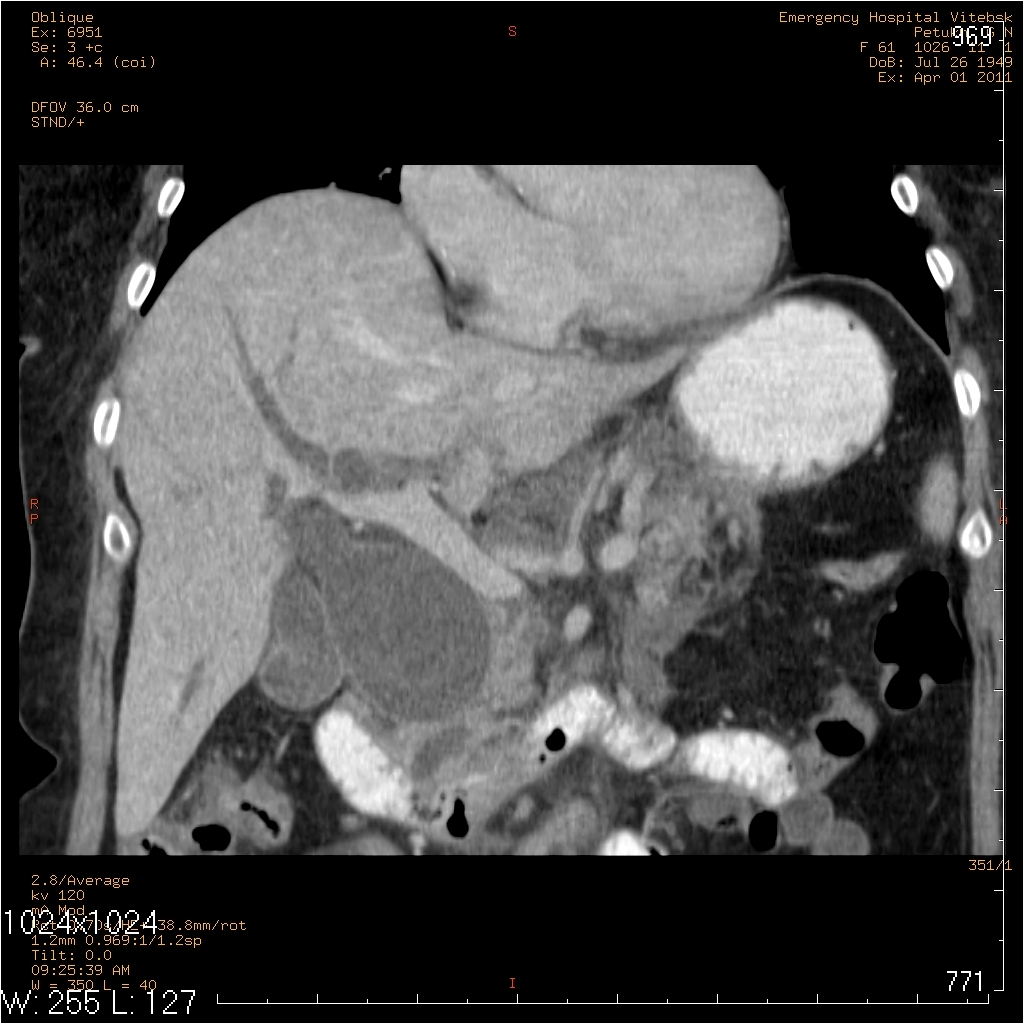

жалобы на периодические боли в правом подреберье, желтушность кожных покровов. считает себя больной в течении 2лет, когда впервые появились боли в правом подреберье. госпитализирована 25.03., 31.03. произведено МСКТ, реконструктивная операция 31.03.

На МСКТ: Киста холедоха (грушевидной формы ~95х50мм). ЖКБ: холецистит, холедохолитиаз (в области БДС дефект наполнения просвета 12пк, расширение вирсунгова протока до 10мм). Билиарная гипертензия. Отёчный панкреатит, парапанкреатит.

На операции: Киста холедоха (терминальный отдел холедоха 2мм). ЖКБ: хр.холецистит, холедохолитиаз (конкременты до 4мм). Стеноз папилы 3ст. (блокада вирсунгова протока, общий желчный и панкреатический протоки впадают в двенадцатиперстную кишку по отдельности). Острый панкреатит, парапанкреатит.